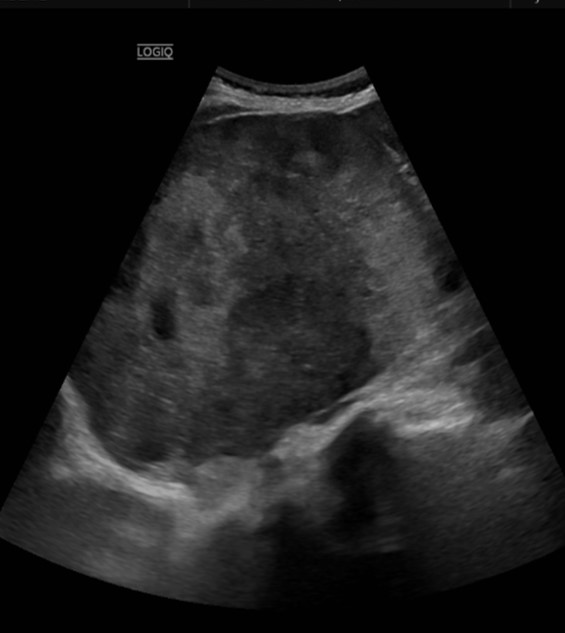

- Ecografía abdominal: Masa sospechosa en región renal/suprarrenal derecha.

- TAC toracoabdominal: Masa sólida de gran tamaño en región hepatorrenal, posiblemente de origen suprarrenal, acompañada de múltiples metástasis pulmonares.